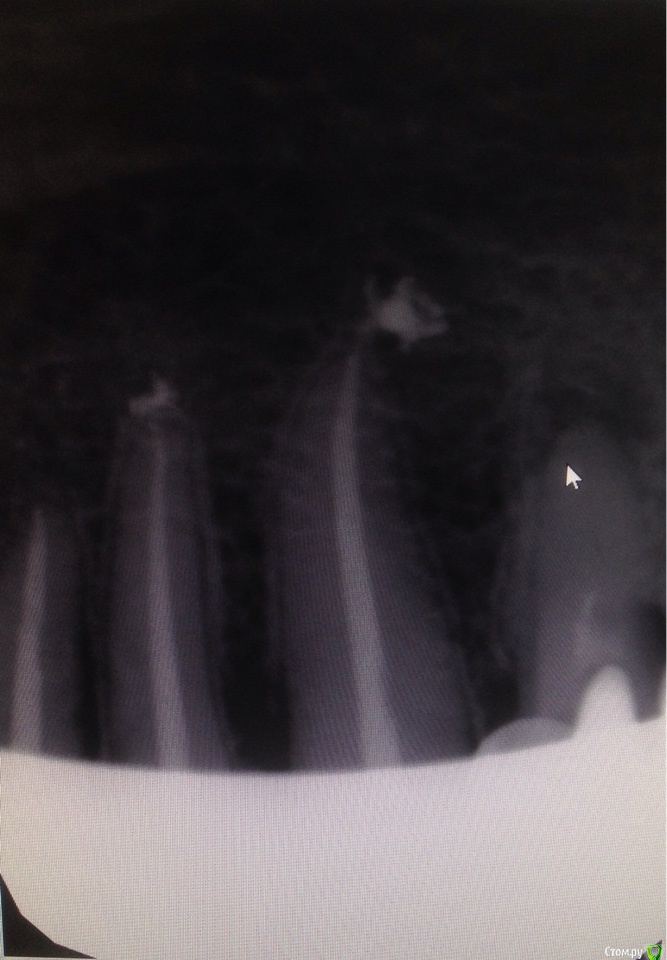

Евгения 66 Опубликовано 20 января, 2015 Автор Поделиться Опубликовано 20 января, 2015 (изменено) Справедливое замечание администратора принимаю :-)Сегодня сделала снимки повторно в другой клинике,правда,в электронном виде получить не удалось,только на рентгеновской плёнке. Сфотографировала,как смогла ( муж держал перед лампой,а я снимала :-). Но даже сама увидела как бы " брызги " цемента ниже корневых каналов. По ощущениям:если зубы не трогать,не болят,но если сверху совсем слегка постучать,больно,и боль потом " висит " ещё пару минут. 33-43 более чувствительны,чем 32. Чувствителен также старый "пенёк" 45,который был запломбирован ещё в 92 г.и стоял под старым снятым 12.01.м/к мостом. Каналы 32-43 пломбировали 09.01.,то есть 12 дней назад. 44 удалён 12.01. Вопрос:может ли попадание цемента в кость за пределы корневого канала быть причиной боли при постукивании или это нормальное следствие пломбировки канала? Может ли боль отдаваться от лунки удалённого 9 дней назад 44 зуба?И ещё большая просьба взглянуть на корень и канал 45 в плане его жизнеспособности и необходимости перепломбировки канала. Большое спасибо и простите за бестолковый пост от 17.01. Снимки прилагаю. Изменено 20 января, 2015 пользователем Евгения 66 1 1 Ссылка на комментарий

Евгения 66 Опубликовано 25 января, 2015 Автор Поделиться Опубликовано 25 января, 2015 Возвращаюсь к своему вопросу от 17 января. Речь идёт о пломбировке каналов 32-43 зубов. Сначала у меня не было снимков. Потом не сумела прицепить. Потом решила,что задала вопрос не в том разделе и повторила его,уже с снимками в Терапии. Теперь понимаю,что так нельзя,только голову всем заморочила. Простите. Повторю вопрос:на снимках видно,что пломбировочный материал вышел за пределы двух корней,насколько понимаю,ниже уровня верхушки канала,то есть в кость. Док.сказала,что это не пломбир.материал,а кальций и что он выведен в лечебных целях,так как на снимках есть затемнение,свидетельствующее о воспалительном процессе (я,правда,этого затемнения не увидела ). Ещё сказала,что не о чем беспокоиться и что через пол года кальций рассосётся и на снимке его уже не будет. Депульпация и пломбировка всех 5 зубов сделана 09.01. под вкладки и м/к коронки. До этого зубы были без дефектов,ни разу не лечены. Буду очень благодарна за Ваше заключение. Ссылка на комментарий